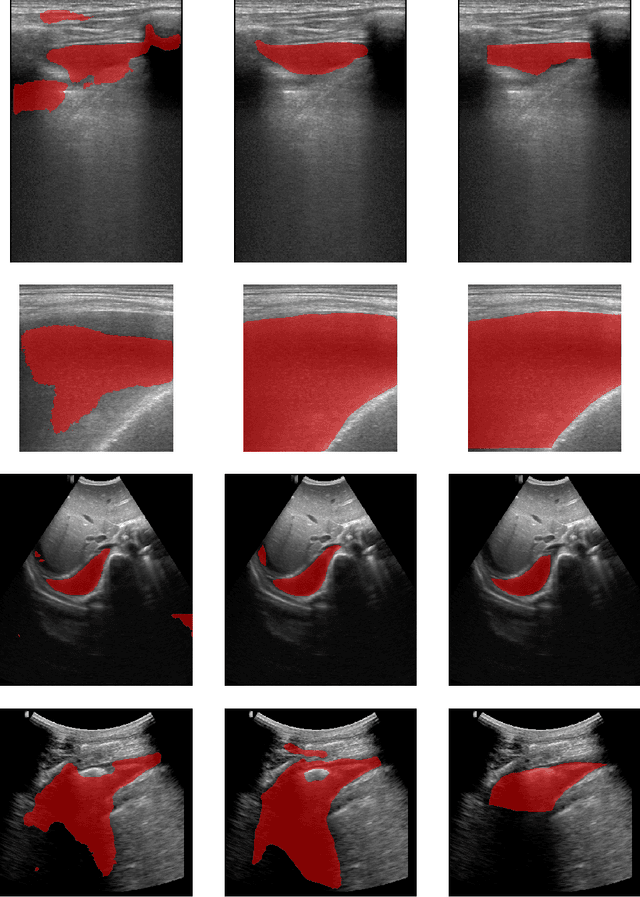

Abstract:In many low-to-middle income (LMIC) countries, ultrasound is used for assessment of pleural effusion. Typically, the extent of the effusion is manually measured by a sonographer, leading to significant intra-/inter-observer variability. In this work, we investigate the use of deep learning (DL) to automate the process of pleural effusion segmentation from ultrasound images. On two datasets acquired in a LMIC setting, we achieve median Dice Similarity Coefficients (DSCs) of 0.82 and 0.74 respectively using the nnU-net DL model. We also investigate the use of coordinate convolutions in the DL model and find that this results in a statistically significant improvement in the median DSC on the first dataset to 0.85, with no significant change on the second dataset. This work showcases, for the first time, the potential of DL in automating the process of effusion assessment from ultrasound in LMIC settings where there is often a lack of experienced radiologists to perform such tasks.